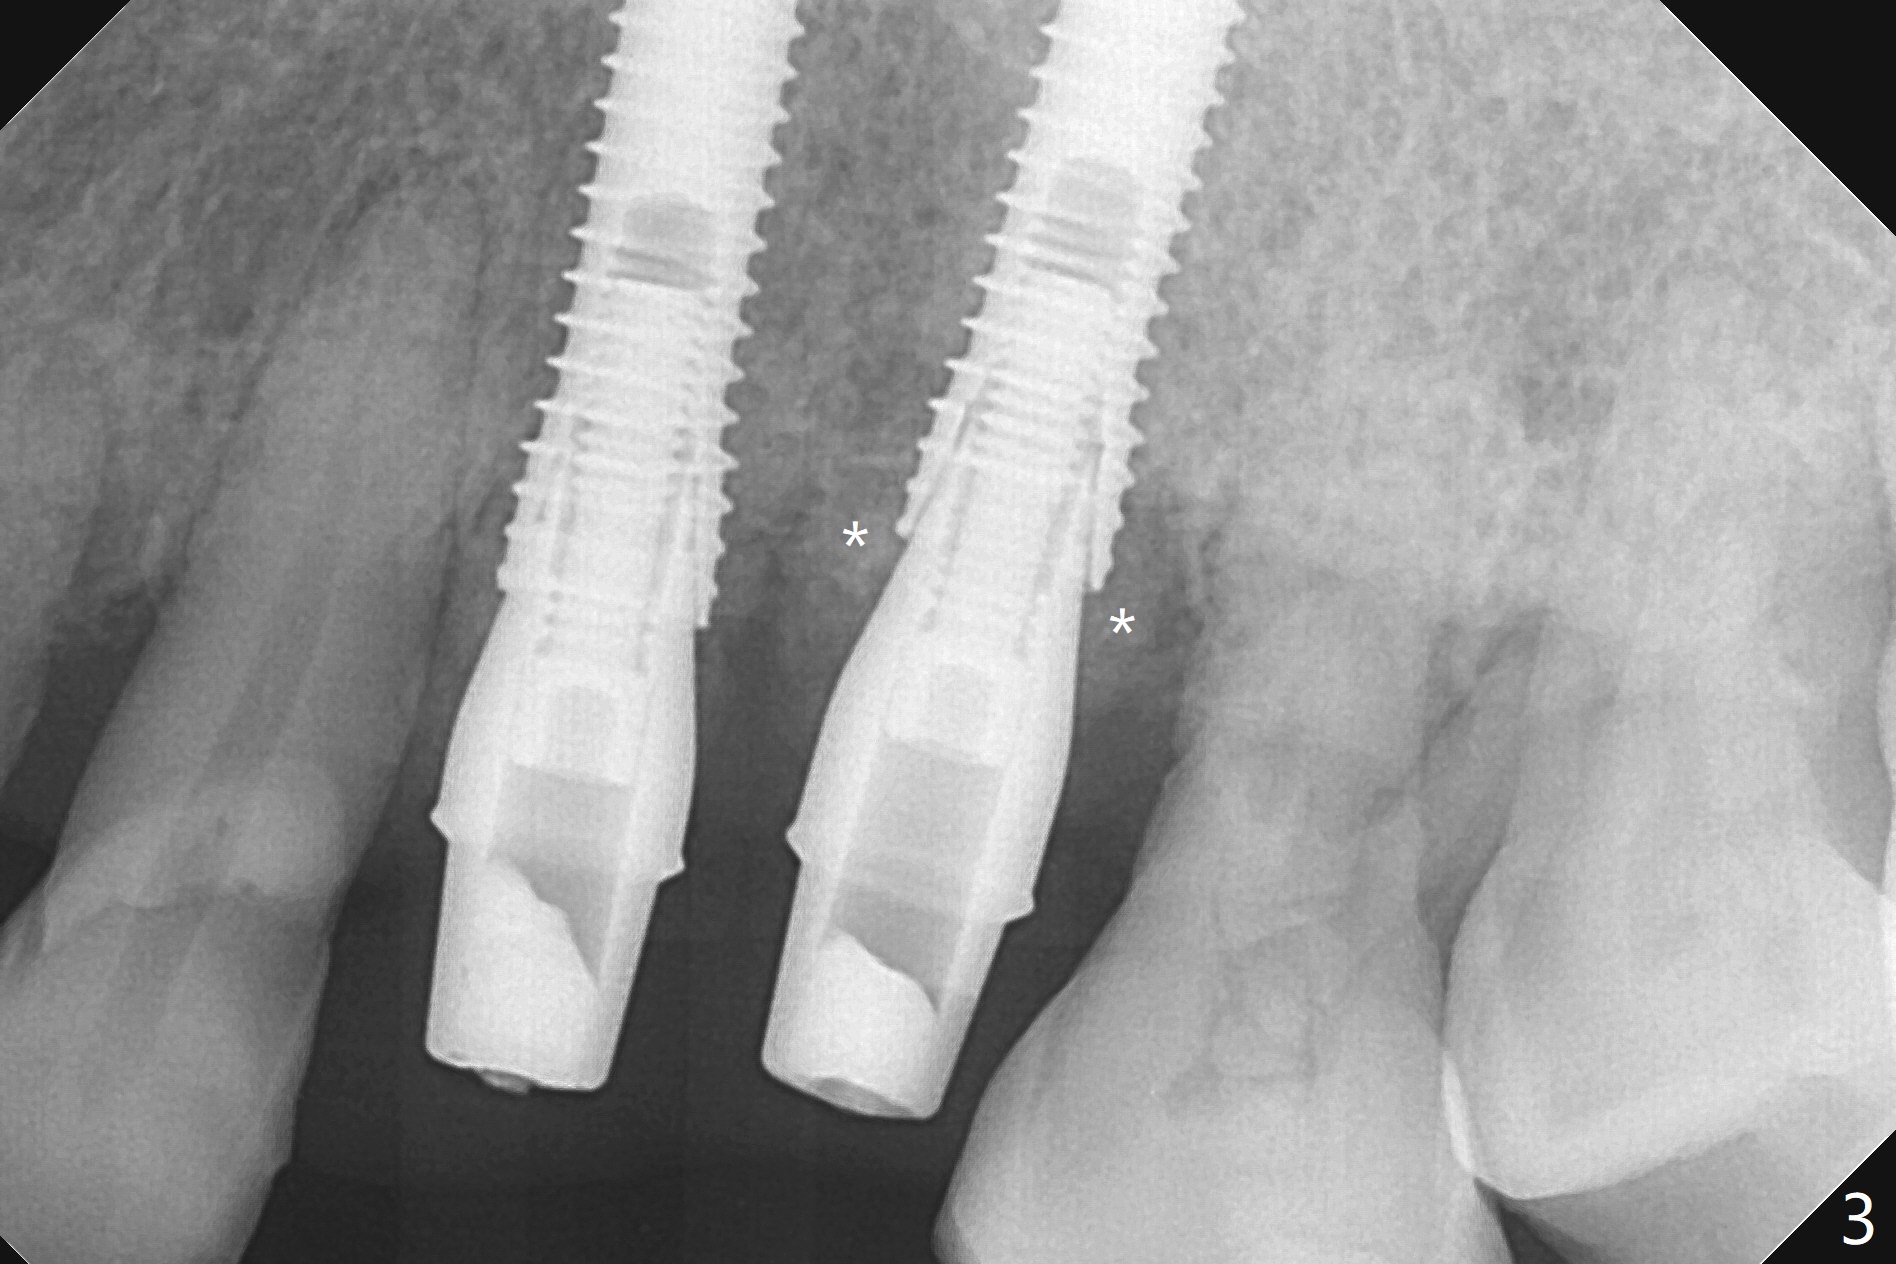

A 66-year-old woman returns to office requesting implant placement at #12 and 13 at an appointment supposed for #5 impression. Depth of osteotomy is 20 mm (gingival level, Fig.1 ( 2mm)). After correction of trajectory at #12 and 3 mm drill for 16 mm at the sites, two of 3.8x16 mm implant are placed with insertion torques of 35 and 15 Ncm, respectively (Fig.2). Before and after change into shorter abutments (4.5x4(4) and (5)), Vera Graft is placed (Fig.3 *). To increase stability, either increase the diameter (4 (Fig.4 at #5) or 4.5 mm instead of 3.8) or length of the implants (red dashed line: sinus floor). Or use dummy implants. The allograft appears to have been incorporated into the host bone nearly 4 months postop (Fig.5). The abutment of the isolate implant at #5 becomes loose twice (Fig.4). To reduce the chance of abutment loosening at #12 and 13, can you make splinted crowns? If the two separate crowns have been fabricated, can you make a slot (with light undercut) in the proximal area of each crown (Fig.6 (occlusal view): S) in addition to access hole (A)? After cementation, composite will be placed in the slots (lock) so that the crowns will not rotate and become loose.